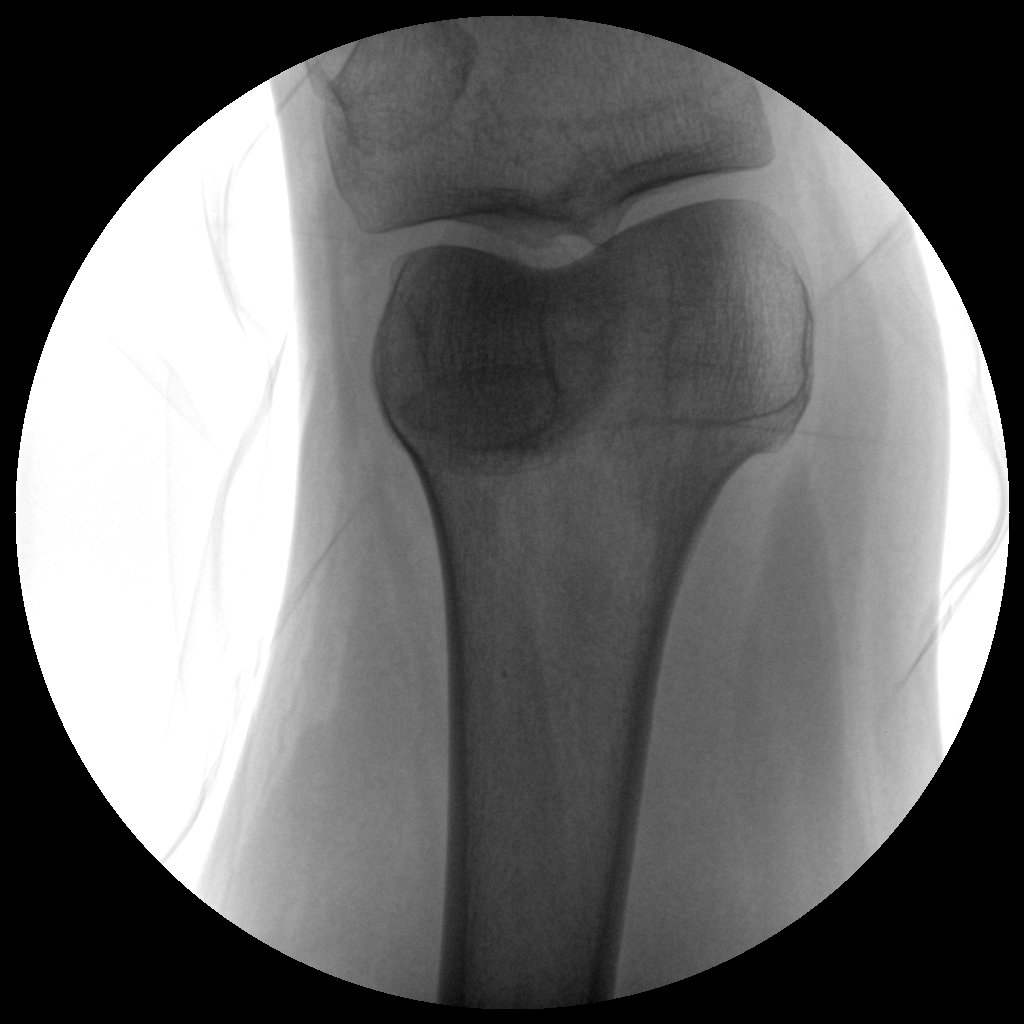

Clinical picture

临床图片